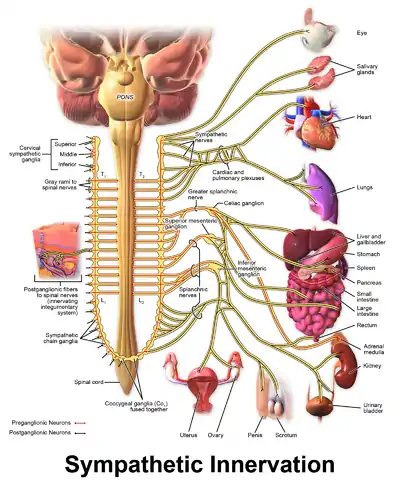

Sympathetic denervation

Some persons with CPVT continue to experience life-threatening arrhythmias despite pharmaceutical therapy. In this case a surgical procedure can be used to affect nerves supplying the heart that communicate using catecholamines.[2] A collection of nerves known as the sympathetic nervous system supply the heart as well as other organs. These nerves, when activated, encourage the heart to beat harder and faster.[28] The sympathetic nervous system uses noradrenaline, a catecholamine, as a chemical messenger or neurotransmitter, which can promote arrhythmias in those with CPVT.[2]

To prevent this, a region of the sympathetic nervous system can be intentionally damaged in an operation known as cardiac sympathetic denervation or sympathectomy.[29] While the sympathetic nervous system feeds into the heart from both sides, often only the left sided nerves are targeted during sympathectomy, although destruction of the nerves on both sides may be required.[29] Through this process, sympathectomy is effective at decreasing, but not abolishing, the risk of further life-threatening arrhythmias.[4]